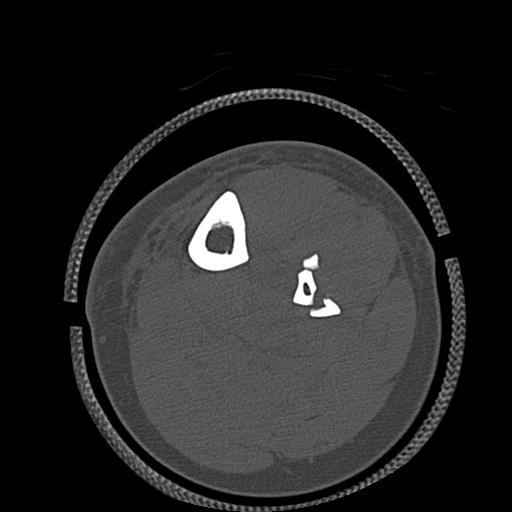

49554 3/13 膝 4R 3/16 4R 1/18 2R 78歳男性 膝蓋骨骨折

100612 11/25 1/20 右膝 2R 84歳女性 右TKA

91983 11/16 左膝 2R 11/18 2R 55歳男性 脛骨骨切り術